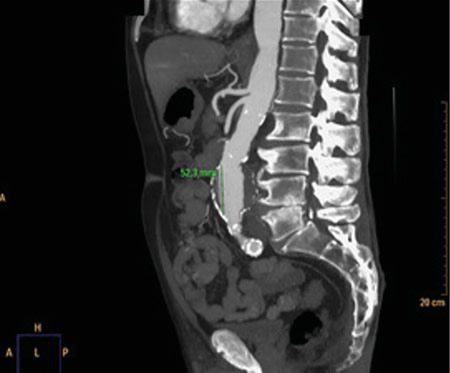

Respecto a las pruebas complementarias, en la analítica sanguínea, se halla una PCR de 39,1 mg/l, leucocitosis de 21.300/mm3, con 88 % de neutrófilos, y una hemoglobina de 10,5 g/dl. En la radiografía pélvica no se evidencian hallazgos patológicos. Debido a la hipotensión, se decide realizar un TC abdominal (Figuras 1 y 2), en el que se objetiva un aneurisma de aorta infrarrenal roto, con diámetro de 50 x 52 x 48 milímetros, a 50 mm de arteria renal derecha y a 65 mm de arteria renal izquierda, craneal a la bifurcación ilíaca. Asimismo, se aprecia un hematoma retroperitoneal en contexto de sangrado en parte posterior de la aorta, que infiltra el músculo psoas ilíaco izquierdo, justificando la clínica de coxalgia con irradiación izquierda. Se contacta con cirugía vascular, interviniéndose de forma urgente, con buena evolución posterior.

Fig. 1. TC coronal de aneurisma de aorta abdominal.

Fig. 2. TC transversal de aneurisma de aorta abdominal.